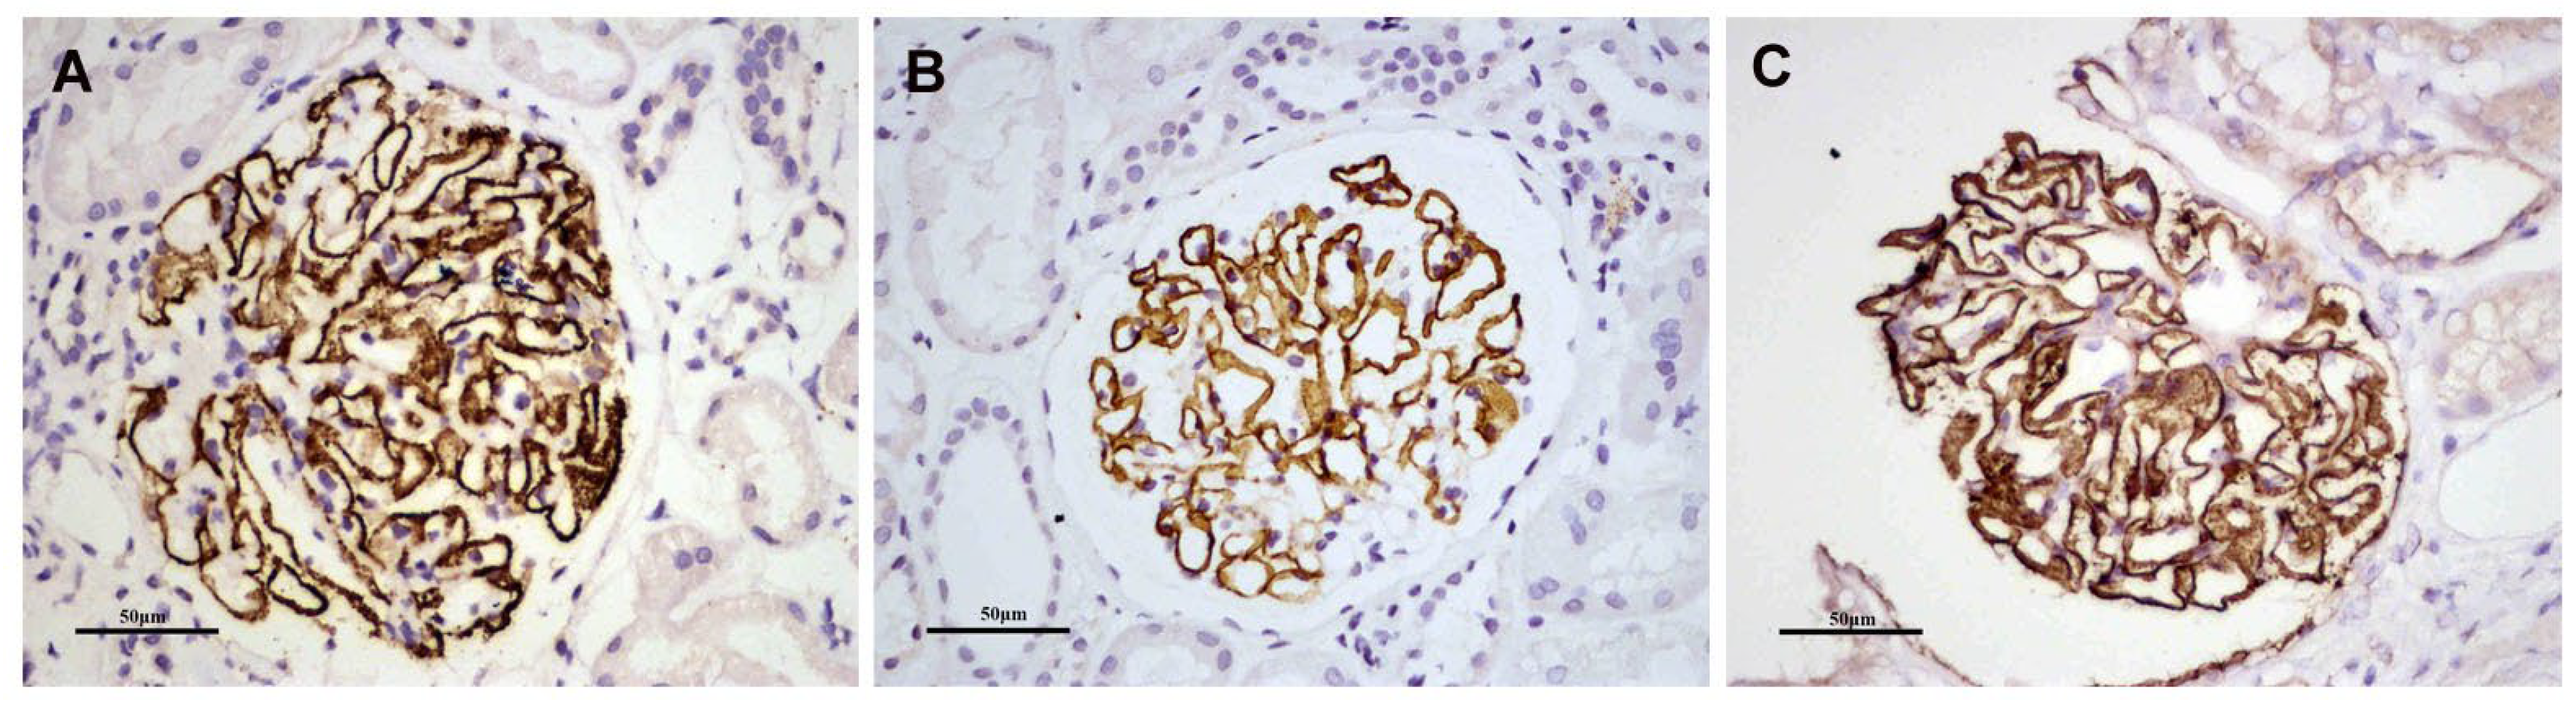

KM55 was deposited mainly in the mesangial and occasionally capillary areas in 20/85 (23.5%) patients with PMN/IgAN, but in 0% (0/29) of patients randomly selected from the PMN/IgA deposition group. Granular positive staining of KM55 by IF occurred along the glomerular mesangial and capillary area in patients with PMN/IgAN (Figure 3). The intensity of glomerular KM55 in the PMN/IgAN group exhibited 0/1+/2+/3+: 65 (76.5%)/8 (9.4%)/10 (11.8%)/2 (2.4%), Table 3 and Figure 3).

Figure 3.

Representative images of immunofluorescence staining for KM55 in patients with PMN/IgAN, (A) Negative, (B) 1+ intensity, (C) 2+ intensity, (D) 3+ intensity. Positive staining of KM55 3+ (F) by immunofluorescence along the glomerular mesangial and capillary area in the same section with IgA positive staining (E). (G) KM55 and IgA colocalized completely along the glomerular mesangial and capillary area. The corresponding two-dimensional (2D) fluorograms have been included to confirm the degree of co-localization (H: Pearson’s correlation 0.9182, Overlap coefficient 0.9245;). (A–G: original magnification ×200).

As 20/85 (23.5%) patients in the PMN/IgAN group presented with granular positive staining of KM55 along the glomerular mesangial and capillary areas, we further investigated the colocalization of KM55 and IgA. KM55 and IgA along the glomerular mesangial and capillary areas (Figure 3). To quantify the colocalization, two-dimensional (2D) fluorograms have been included to confirm the degree of co-localization (Figure 3H: Pearson’s correlation 0.9182, Overlap coefficient 0.9245).